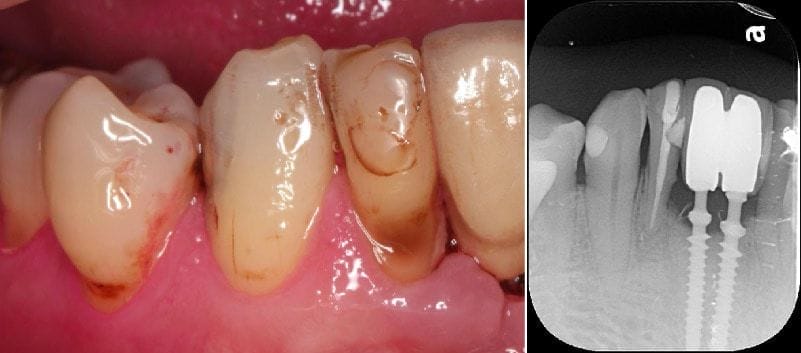

而在前年的某次回診,Mr.Hsieh說他的右下植牙旁的牙齒崩了一塊。經口內和局部X光片檢查,其實右下側門牙是根管治療後的牙齒,右下犬齒也曾用傳統樹脂填補過。我當時是建議他可以用數位牙科全瓷貼片的技術把兩顆牙齒修復。因為這樣比傳統假牙需要把整個牙齒修小,貼片的方式僅需修磨0.5mm左右的厚度,能保留更多健康牙齒齒質。

治療前

圖示:治療前Mr.Hsieh的右下側門牙、右下犬齒及口內掃描X光片